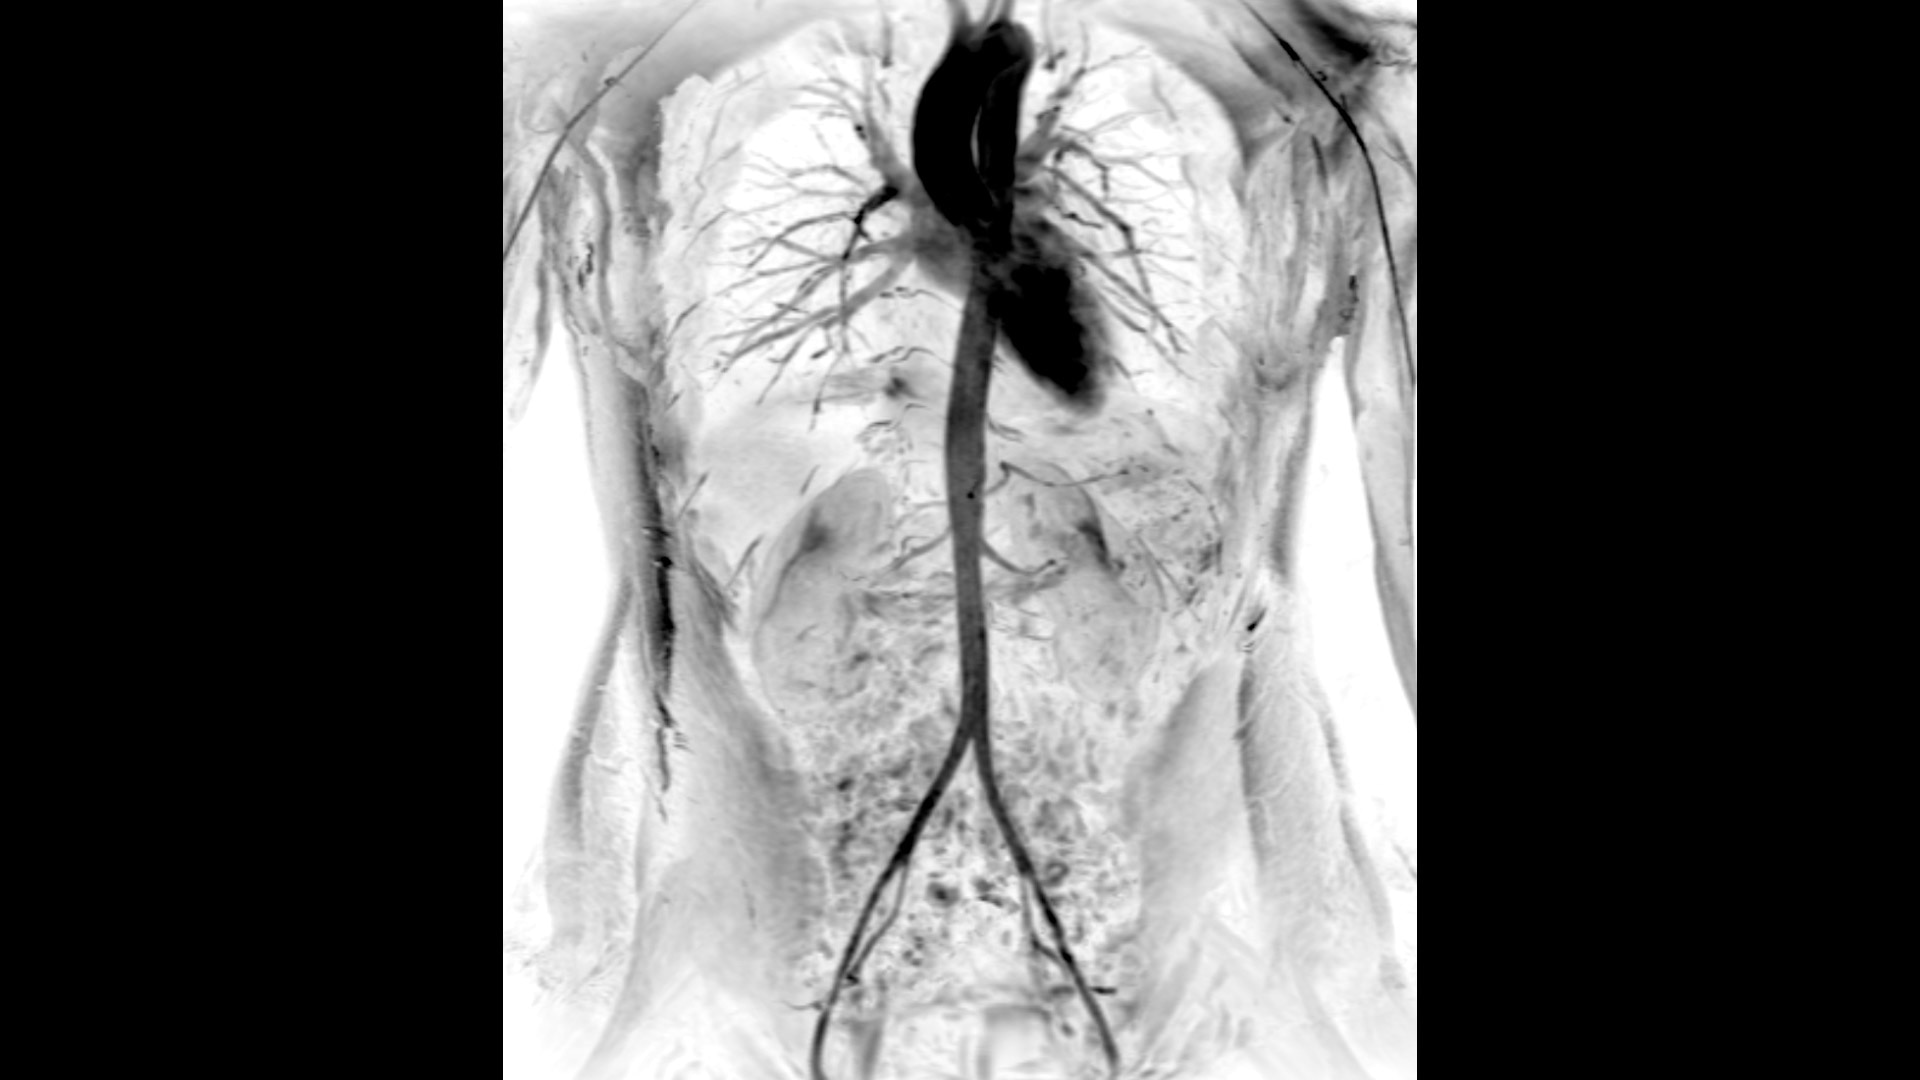

Clinical excellence

Coil flexibility makes it easier to get closer to the patient, providing more coverage compared to other coils